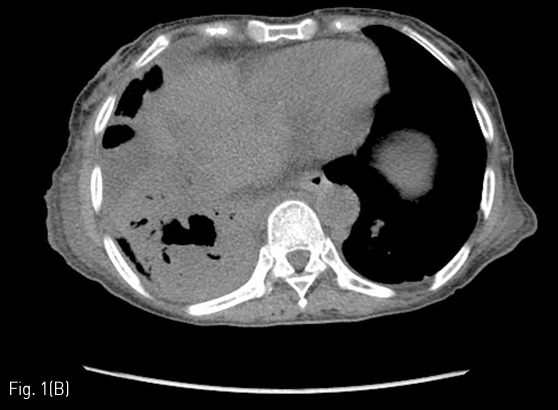

Fig 1B

64-year-old woman with fever, biliptysis and dyspnea. An axial CT scan shows recurred tumor along resection margin of left lobe of liver and dilated bile ducts (A), and a lung abscess in right lower lobe (B).